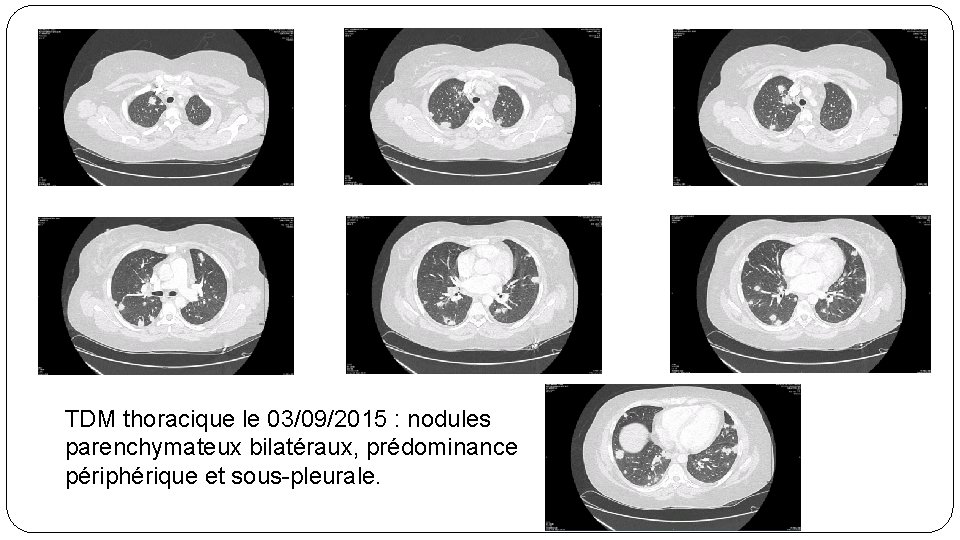

TDM thoracique le 03/09/2015 : nodules parenchymateux bilatéraux, prédominance périphérique et sous-pleurale.